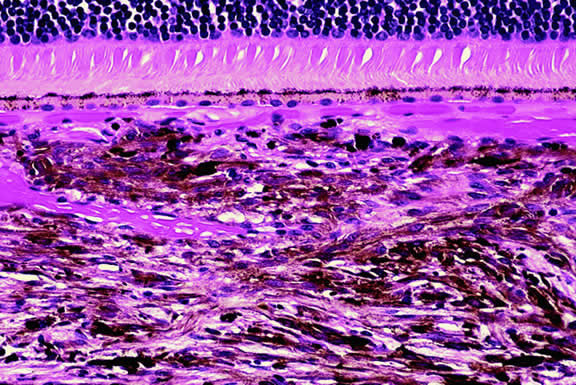

Ophthalmoscopic examination of a choroidal melanoma typically reveals a sessile or dome-shaped pigmented mass located deep to the retina (Figs. 16, 17, and 18). There often is an associated secondary nonrhegmatogenous serous detachment of the retina. Orange pigment may be located on the surface of smaller lesions.80,81 Tumors vary in pigment content and may be heavily pigmented or totally amelanotic. The differentiation of a totally amelanotic melanoma from uveal metastasis, hemangioma, lymphoma, or osteoma may be difficult. Compared with metastasis, melanoma usually is more highly elevated and drusen and RPE proliferation more evident on its surface. Ophthalmoscopy also typically shows well-defined vessels within melanoma.48 Ancillary studies such as fluorescein angiography and ultrasonography may be necessary to make the diagnosis.

Many choroidal melanomas have a characteristic mushroom or collar button configuration that results when the tumor breaks through Bruch's membrane (Figs. 19, 20, 21, and 22). In such cases there is often secondary choroidal, subretinal, or vitreous hemorrhage. Dilated, intrinsic vessels often are evident in the mushrooming dome of nonpigmented melanomas. The vessels are obscured in more pigmented tumors.48

Fig. 19. Fundus photo of mushroom-shaped choroidal melanoma with nonpigmented dome. Configuration indicates that tumor has ruptured through Bruch's membrane.

Choroidal melanomas produce abnormalities in the overlying retinal pigment epithelium including atrophy, hyperplasia, and the formation of drusen and drusenoid material.92 The overlying retina often shows photoreceptor loss and may develop cystoid edema. The latter tends to be more common in slower growing lesions, especially choroidal hemangiomas. After Bruch's membrane has ruptured, the vessels located in the mushrooming head of the tumor are often quite prominent, reflecting vascular stagnation caused by the compression at the waist of the tumor (see Fig. 22). Aggregates of macrophages that have ingested periodic acid-Schiff (PAS)-positive lipofuscin pigment and melanin from the damaged retinal pigment epithelium can be found in the subretinal fluid (Figs. 39 to 41). These are evident ophthalmoscopically as clumps of orange pigment that serve as a clinical marker for an actively growing neoplasm.80,81